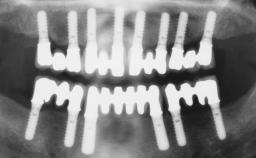

# of Implants 6

Defining Characteristics Fully edentulous upper jaw to be rehabilitated with four or more implants

Modality 6+ implants with immediate loading

Bone Volume Horizontally and vertically sufficient